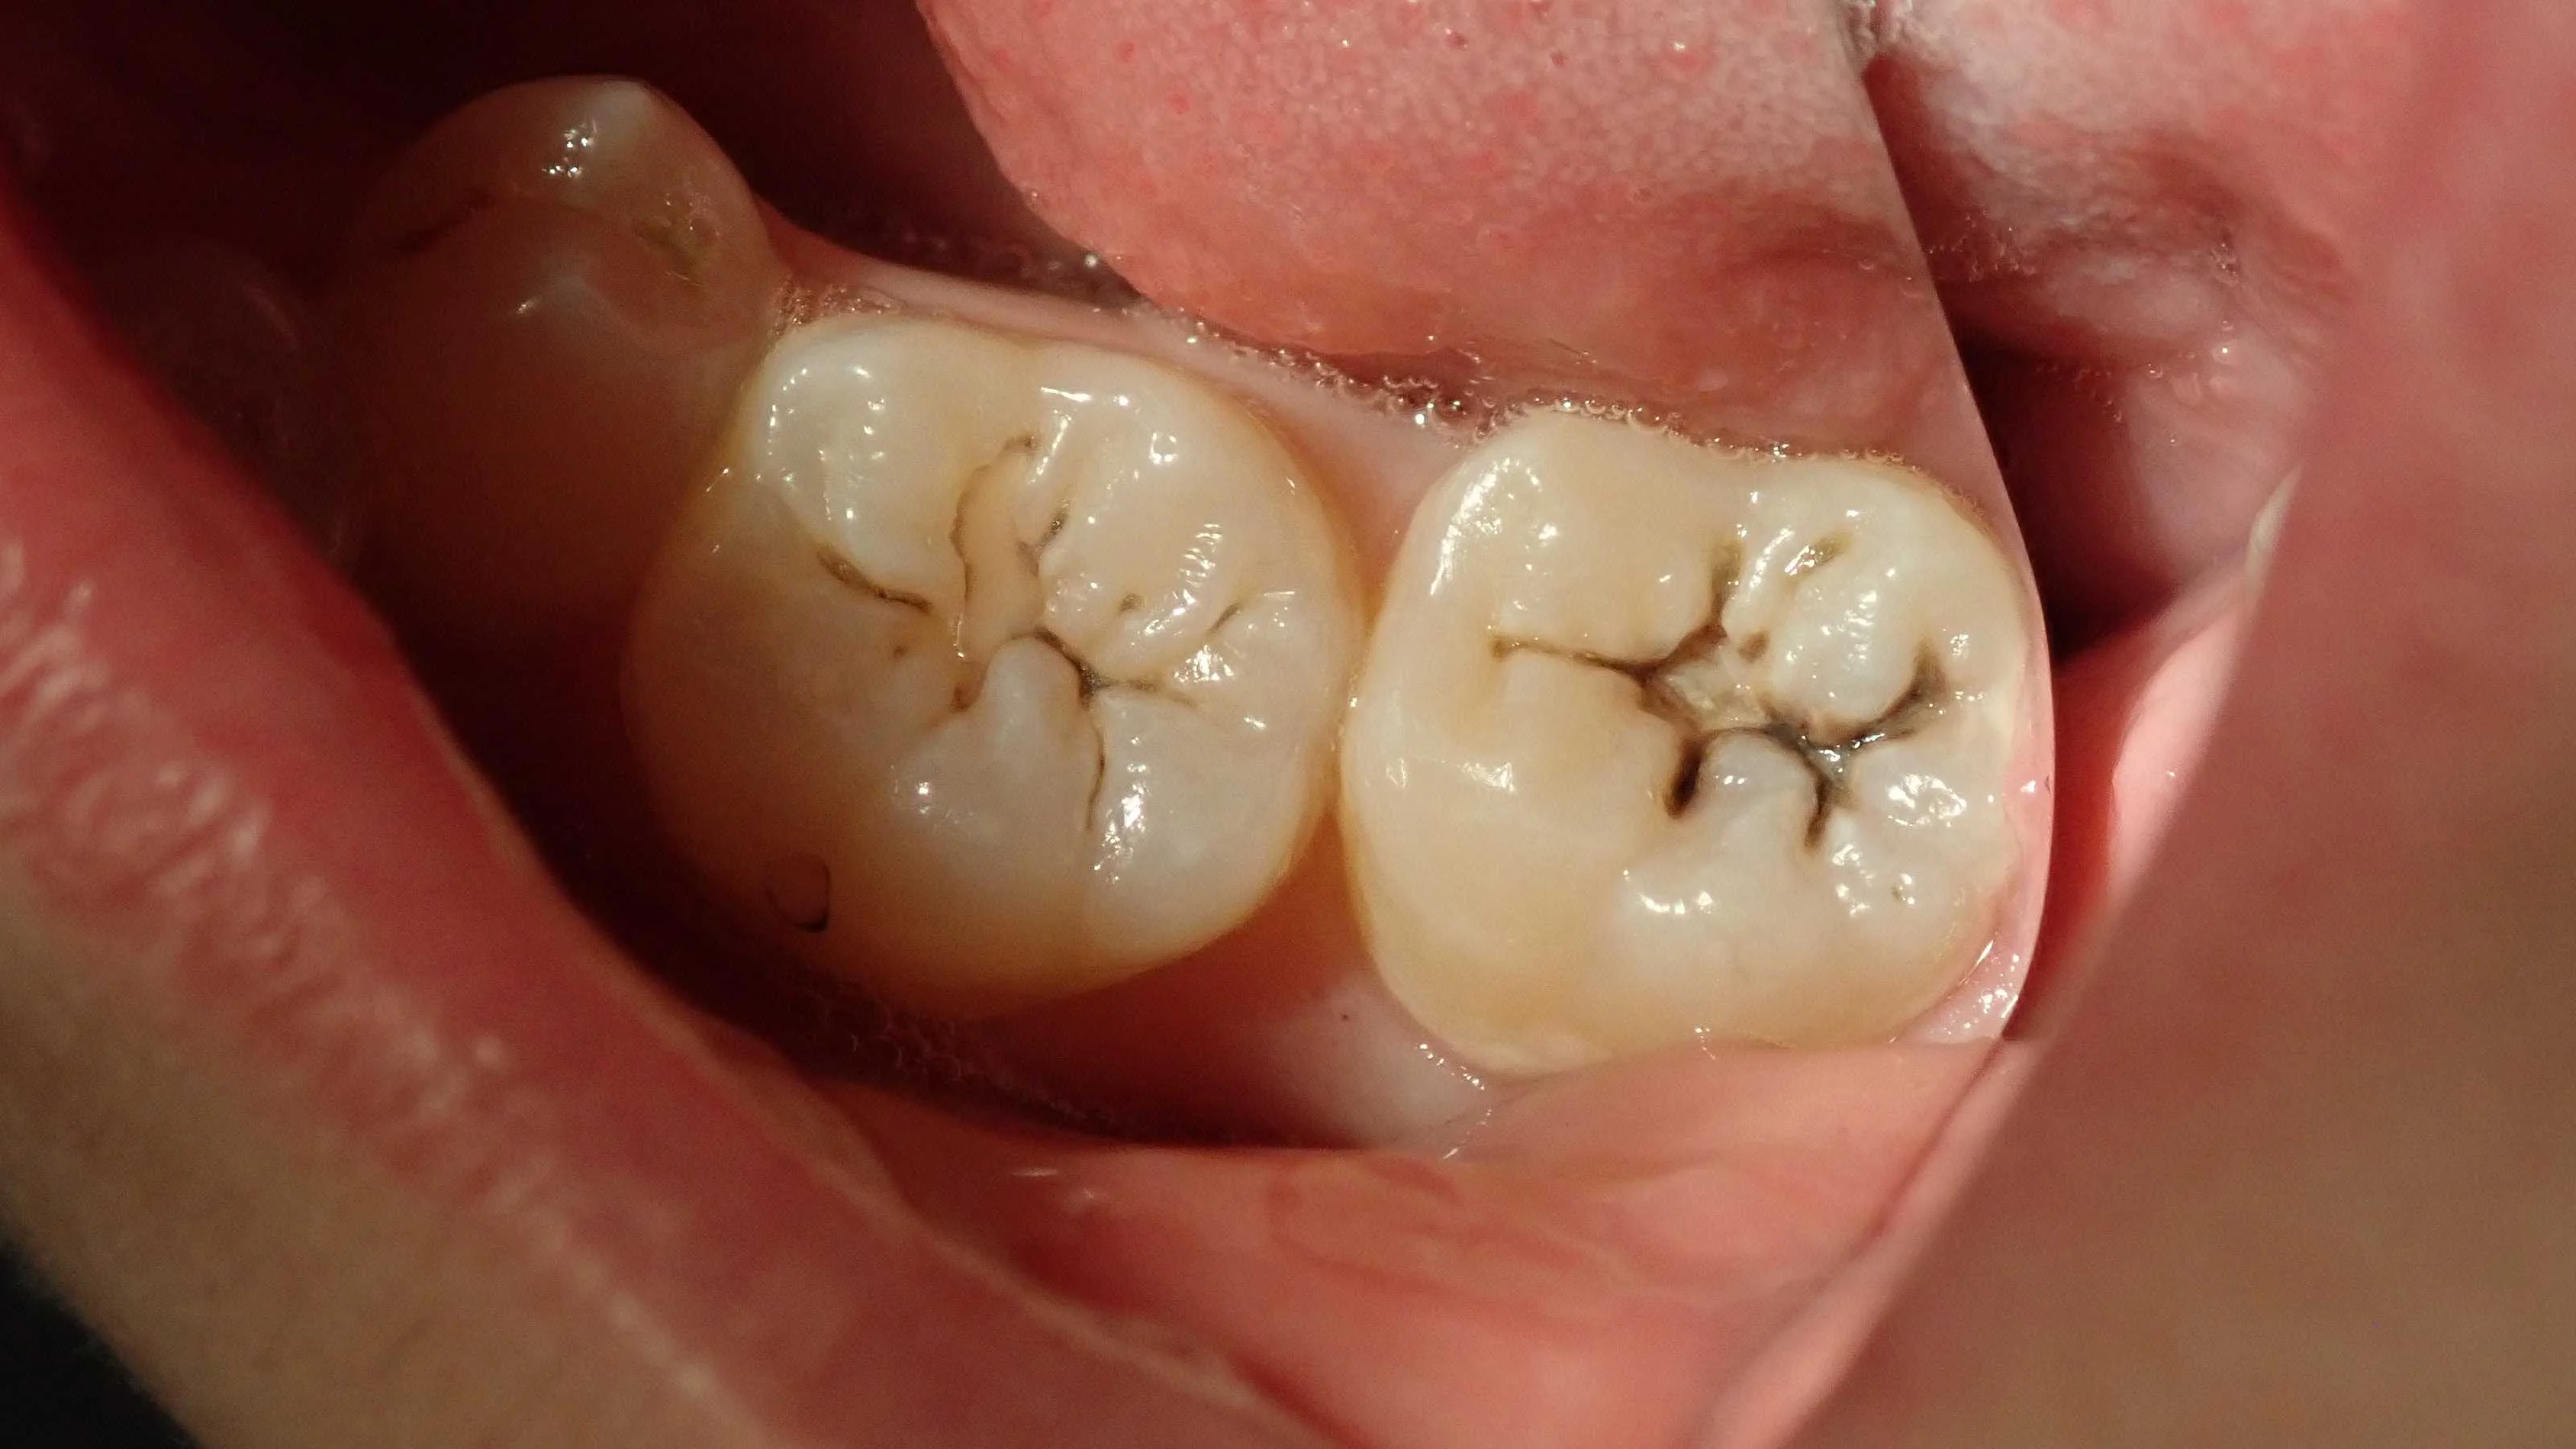

最初の状態がこちらです。

下の奥歯だったので、鏡を入れて撮影しています。

手前はともかくとして、奥のほうは中々な虫歯です。

ちなみに、虫歯の治療が必要かどうかというのは、

肉眼のみでの診断では分かりません。

必ずレントゲンなど、複数の検査を併用して治療が必要かどうかを判断する必要があります。